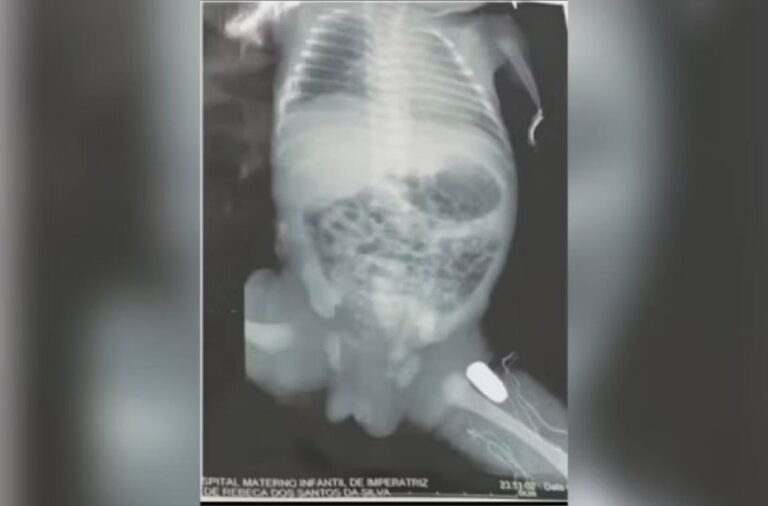

Grávida, adolescente de 16 anos é baleada na barriga

Uma adolescente de 16 anos, grávida de nove meses, foi atingida por uma bala, durante um assalto em Imperatriz no Maranhão.